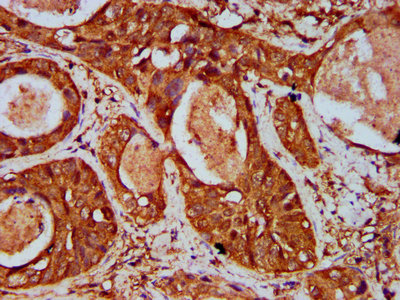

IHC image of CSB-PA823478LA01HU diluted at 1:500 and staining in paraffin-embedded human cervical cancer performed on a Leica BondTM system. After dewaxing and hydration, antigen retrieval was mediated by high pressure in a citrate buffer (pH 6.0). Section was blocked with 10% normal goat serum 30min at RT. Then primary antibody (1% BSA) was incubated at 4°C overnight. The primary is detected by a biotinylated secondary antibody and visualized using an HRP conjugated SP system.